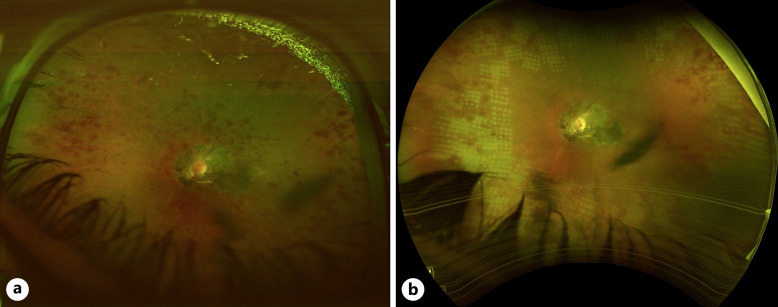

导言:抗磷脂综合征是导致获得性高凝状态的最常见原因之一,与眼部疾病有关,其中最重要的是动脉或静脉闭塞导致的视网膜缺血:我们描述了一例合并视网膜中央动脉和静脉闭塞并伴有视网膜色素上皮增生的单侧视网膜缺血病例。对患者进行了病因检查,发现是抗磷脂综合征:尽管色素上皮增生通常发生在视网膜缺血之后,但还没有研究报告对这种病理现象进行完整的多模态成像,也没有提出解释这种关联的可能机制。

Case presentation: We describe a case of unilateral retinal ischemia in the setting of combined central retinal artery and vein occlusion with associated proliferation of retinal pigment epithelium. The patient was worked-up for the etiology of her presentation which was found to be antiphospholipid syndrome.